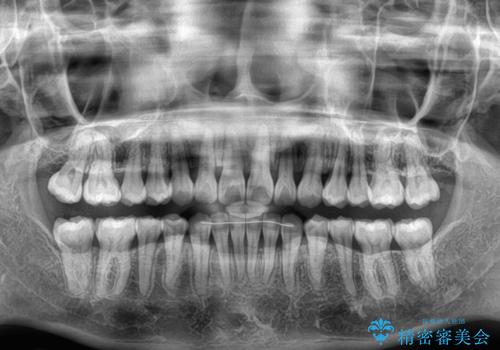

【モニター】上顎前突と奥歯の鋏状咬合 補助装置を用いたインビザライン矯正治療

奥歯の咬み合わせを事前に望ましい位置に改善したことで、インビザライン単独では改善が最も困難な状況を排除することができ、非常に理想的な仕上がりとなりました。